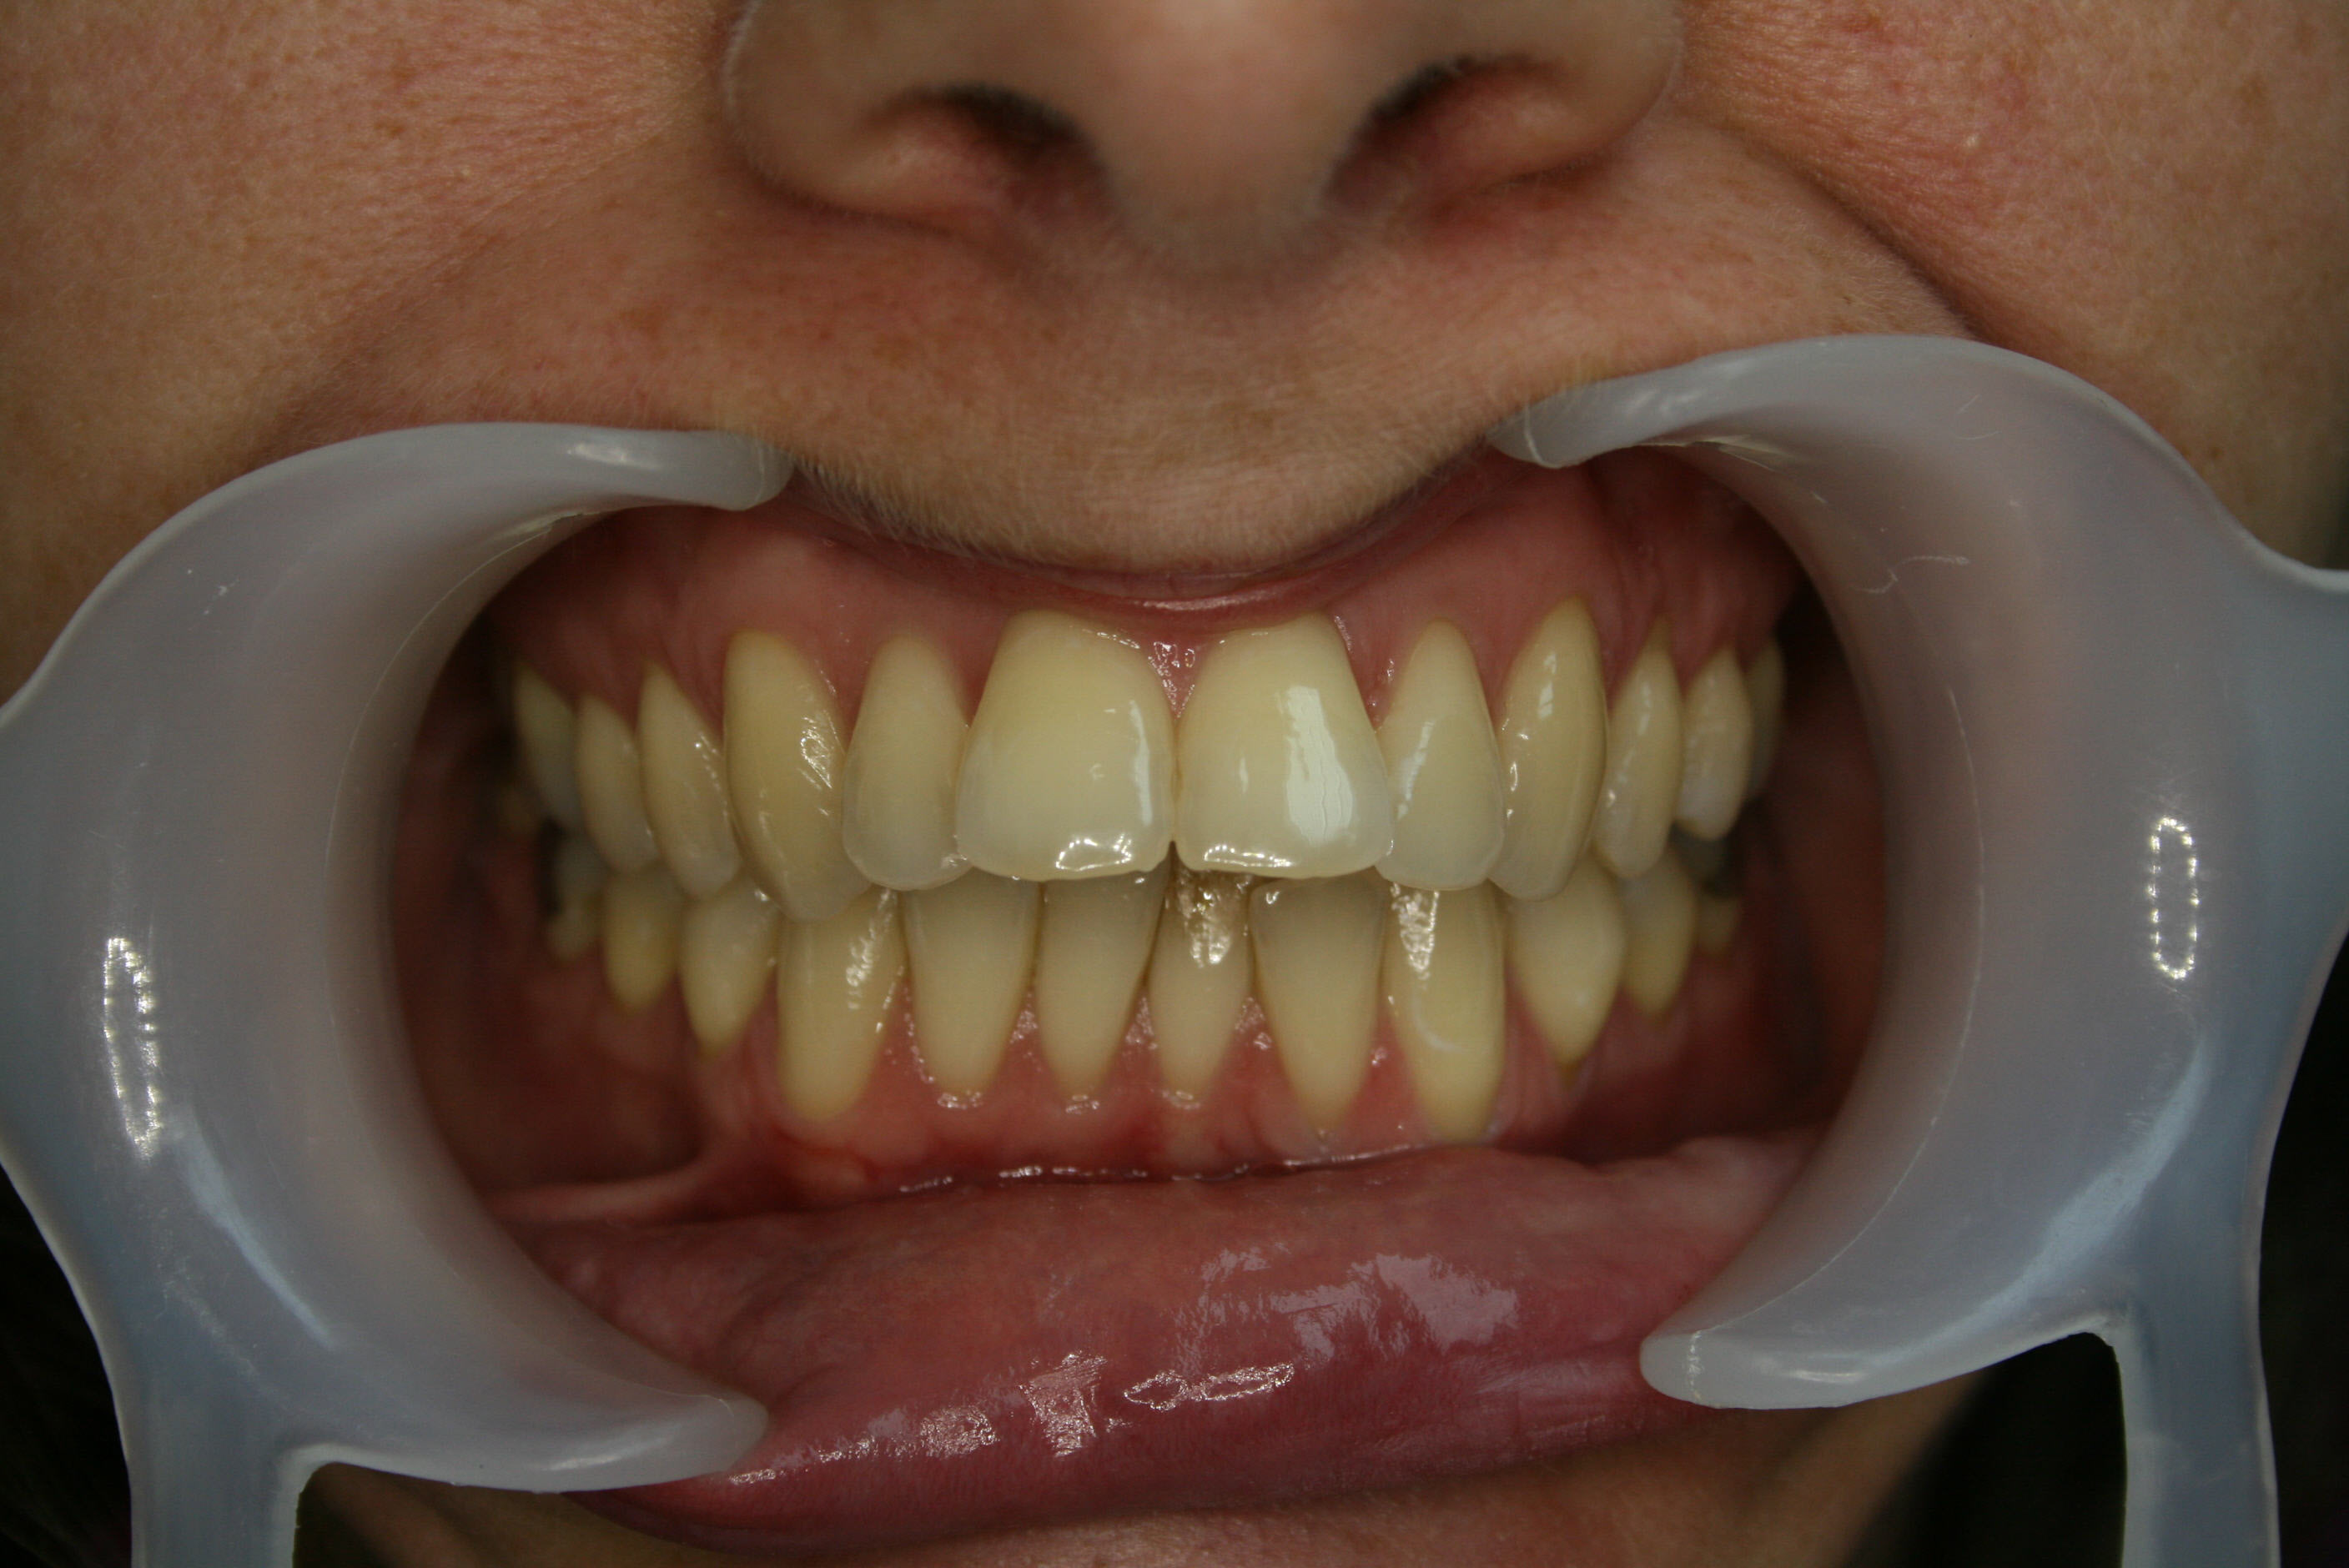

Nach der Behandlung

Die Normalisierung der Achsenstellung der oberen Schneidezähne erlaubte einen entspannten Lippenschluß und ein ansprechenderes Erscheinungsbild der oberen Zahnreihe beim Lächeln.

Die Oberlippe ist nicht mehr so stark vorgeschürzt, der Winkel zwischen Nasensteg und Oberlippe hat sich allerdings vergrößert, was ästhetisch weniger ansprechend ist; dies hätte nur durch eine chirurgische Vorverlagerung des Unterkiefers vermieden werden können. Siehe hierzu auch Fallbeispiel 9.